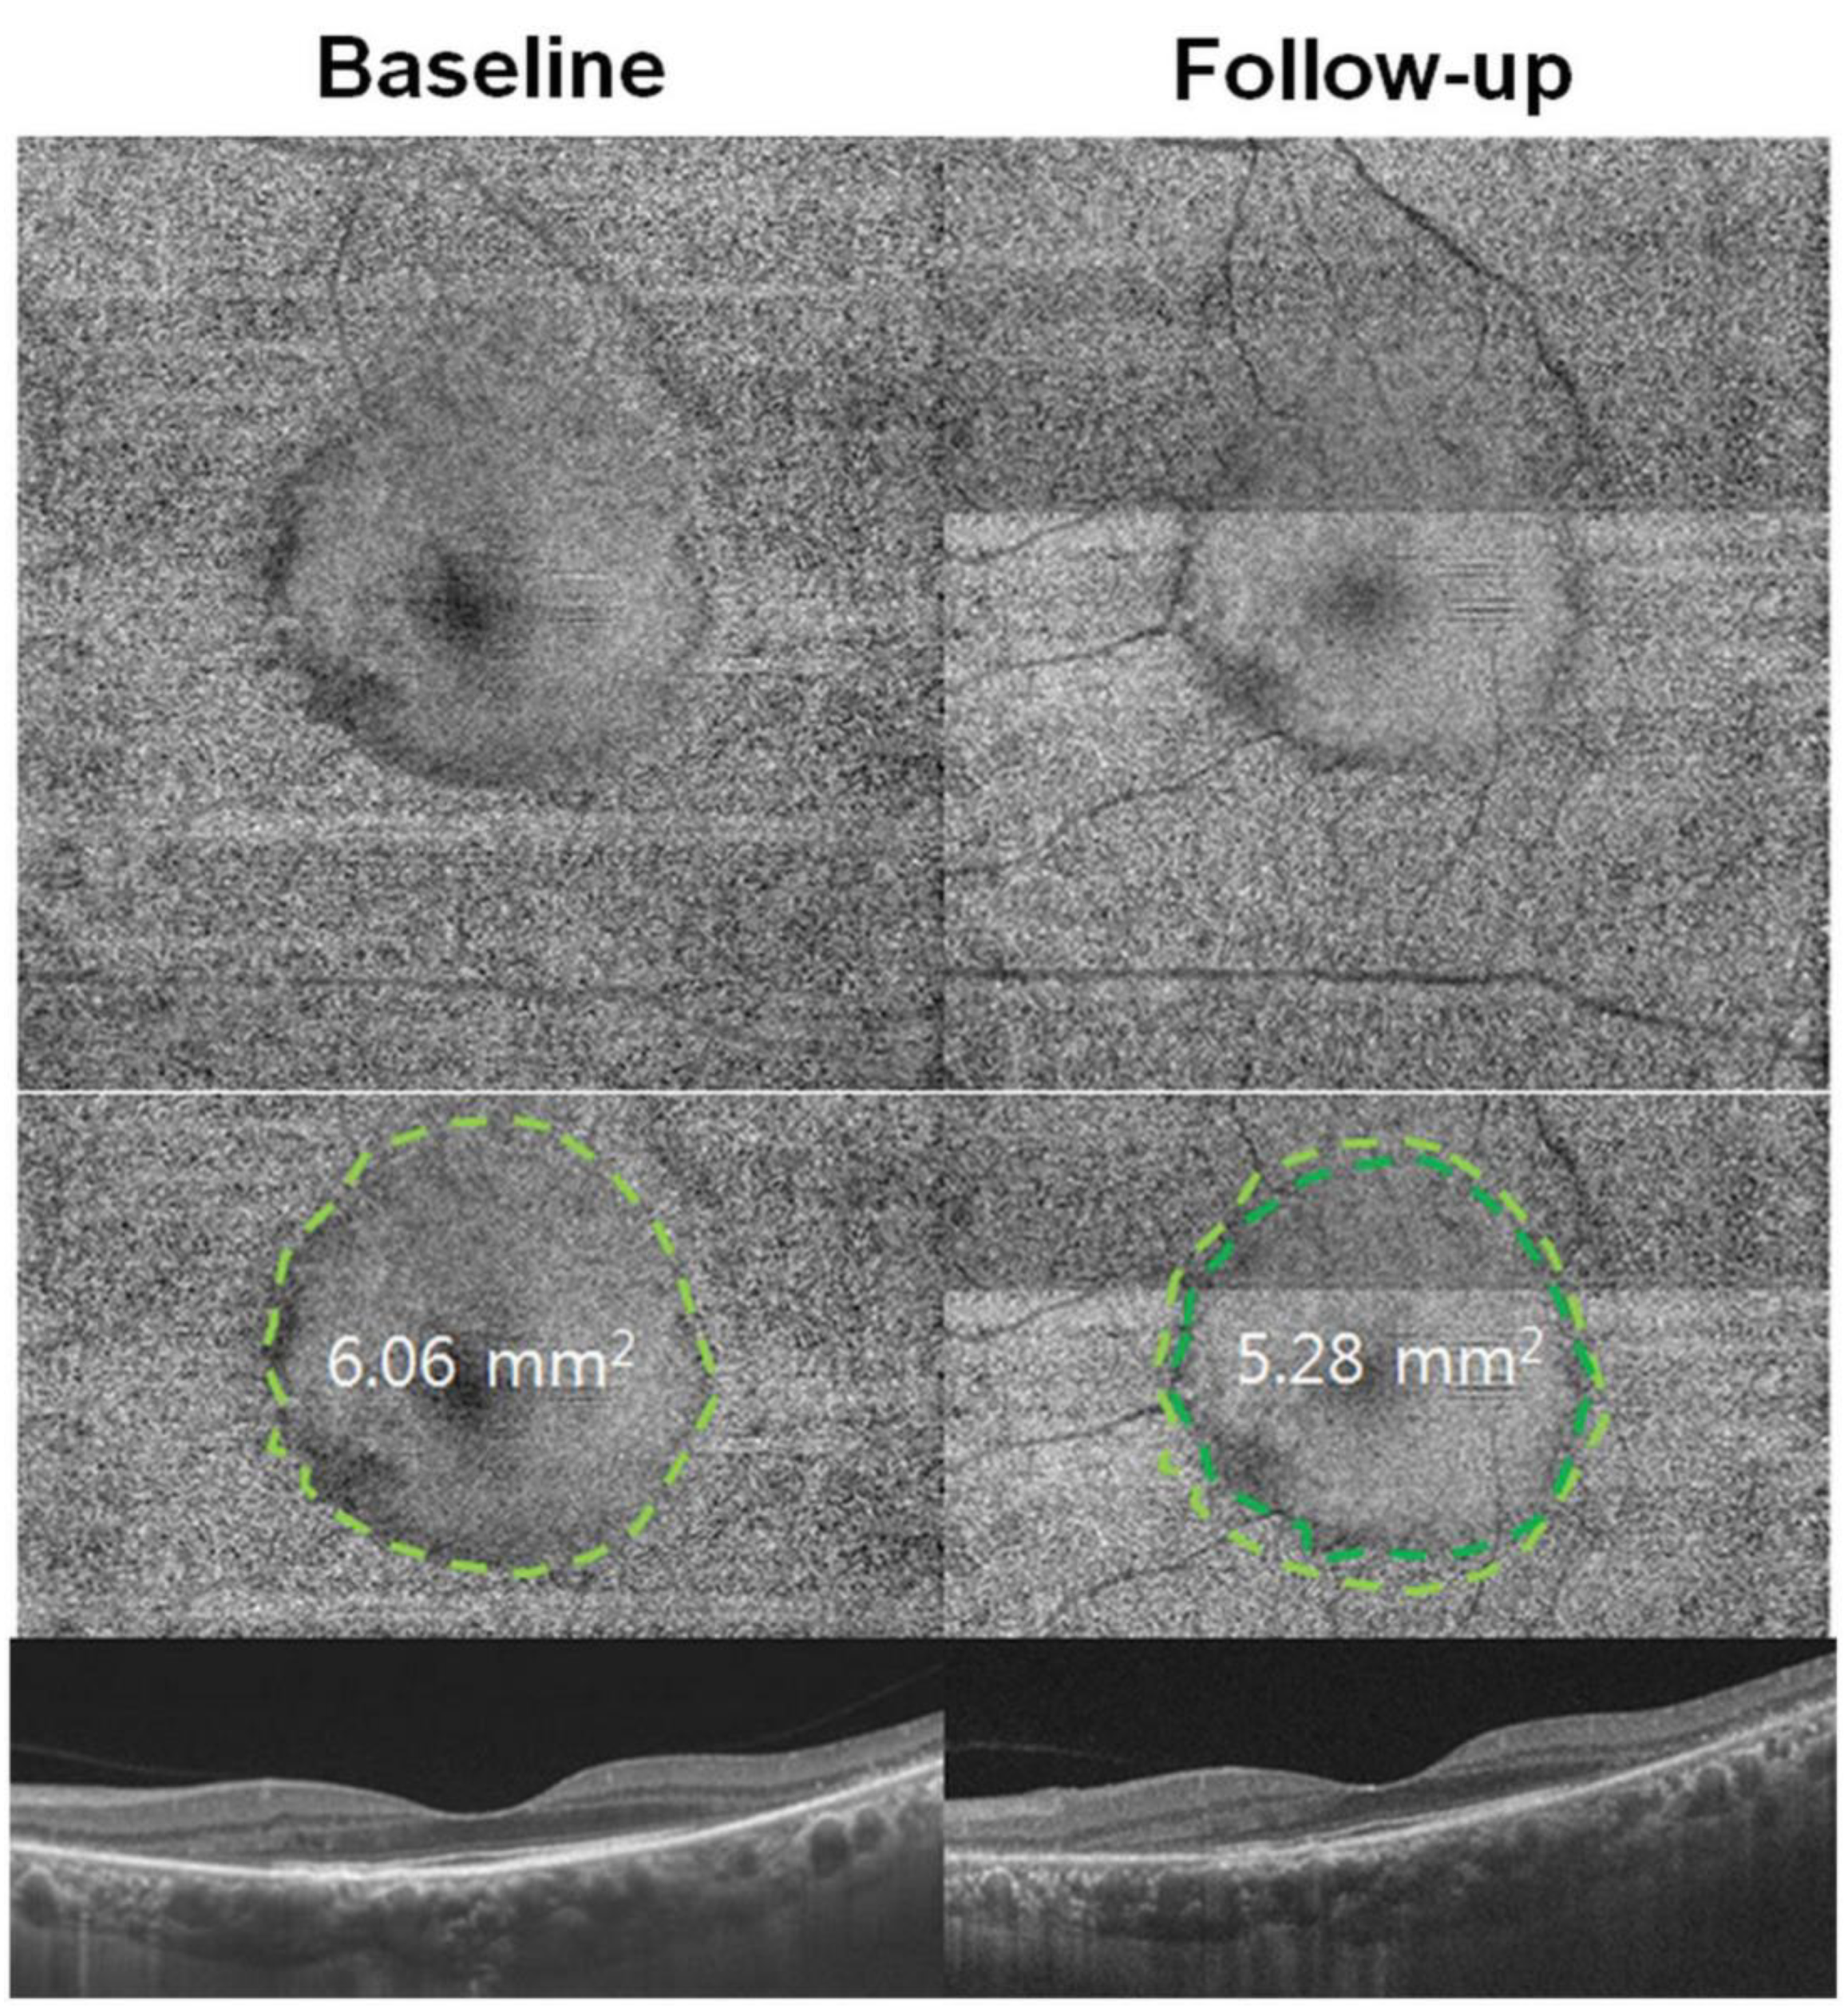

| Minimum intensity analysis |

|

- Stetson, P.F.; Yehoshua, Z.; Garcia Filho, C.A.A.; Portella Nunes, R.; Gregori, G.; Rosenfeld, P.J. OCT Minimum Intensity as a Predictor of Geographic Atrophy Enlargement. Investig. Ophthalmol. Vis. Sci. 2014, 55, 792–800. [Google Scholar] [CrossRef] [PubMed]

- Schmitz-Valckenberg, S.; Fleckenstein, M.; Göbel, A.P.; Hohman, T.C.; Holz, F.G. Optical Coherence Tomography and Autofluorescence Findings in Areas with Geographic Atrophy Due to Age-Related Macular Degeneration. Investig. Ophthalmol. Vis. Sci. 2011, 52, 1–6. [Google Scholar] [CrossRef] [PubMed]

- Allahdina, A.M.; Stetson, P.F.; Vitale, S.; Wong, W.T.; Chew, E.Y.; Ferris, F.L.; Sieving, P.A.; Cukras, C. Optical Coherence Tomography Minimum Intensity as an Objective Measure for the Detection of Hydroxychloroquine Toxicity. Investig. Ophthalmol. Vis. Sci. 2018, 59, 1953–1963. [Google Scholar] [CrossRef] [PubMed]